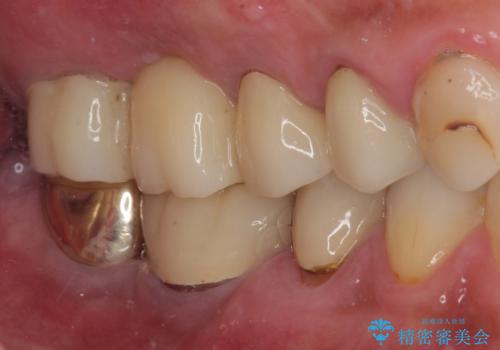

- 土台の歯が割れてしまって、歯がグラグラしているとのことで来院された患者様です。

いずれの歯も抜歯が必要な状態であり、抜歯即時埋入によるインプラント治療を行うこととしました。

右上奥歯は骨欠損の範囲が広いため、抜歯即時埋入は可能であっても、即日で仮歯を装着する即時荷重は難しいと判断されたため、手前の歯まで仮歯を装着することとしました。

強い咬合力により歯根破折を繰り返しているため、即日荷重あるいは早期荷重による他の歯への負担を軽減することが重要となります。

抜歯即時埋入インプラントは、咬合力によるトラブルを回避する、非常に有用な手段となります。